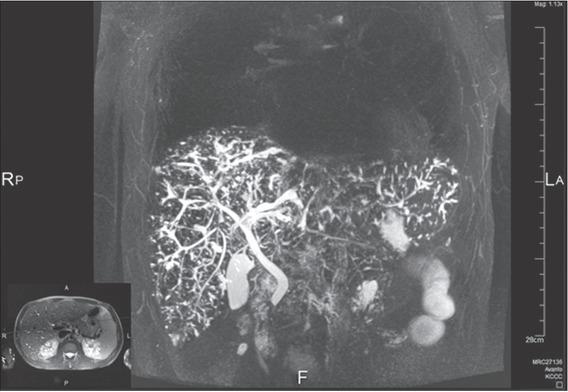

Figure 2